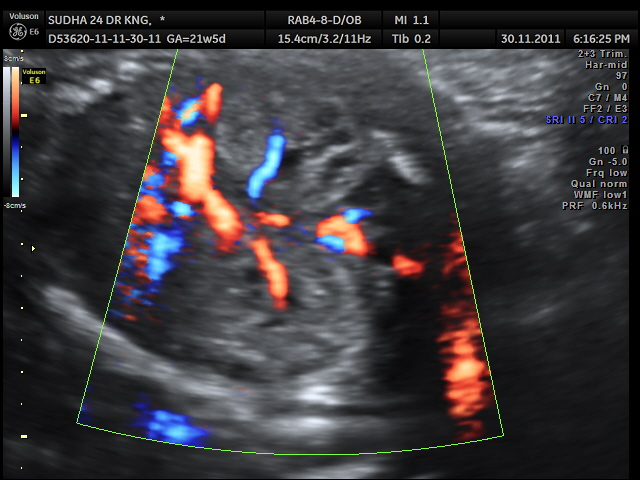

Placentomegaly with placental cysts

enlarged and hyperechoic kidneys